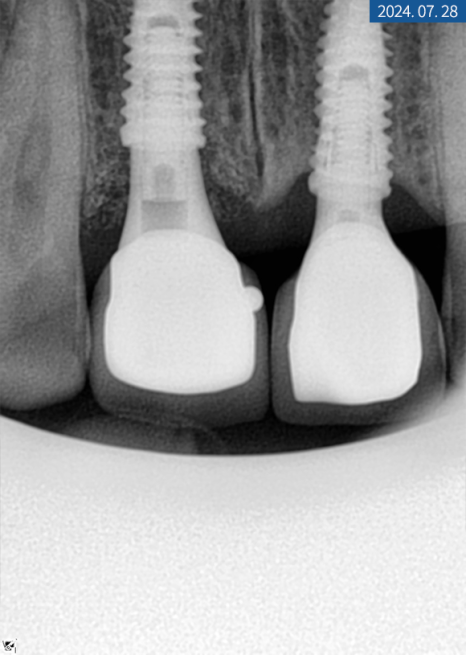

#11번은 인공 나사를 심고 힐링 어버트먼트를

바로 연결해서 잇몸을 만들었습니다.

3개월 후 골 유착을 확인하고

교합과 인상 채득을 한 다음 크라운 제작을 위해

색상 대조 후 기공소에 의뢰했습니다.

좌측과 다르게 우측은

*와이어 템포러리를 만들어서

심미 보강을 도와드렸고

2주 후 커스텀 어버트먼트와 크라운을

알맞게 체결, 수복해 드렸습니다.

한 달 후 치근단 사진을 찍어보니

주위 염증 없이 이식된 자리에

잘 위치하고 있었습니다.